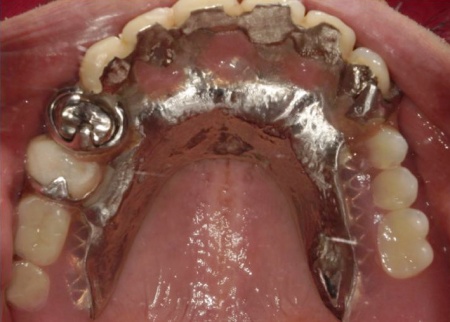

根管治療が終了した上の歯には、オーバーデンチャーの支えとなる内冠(入れ歯を安定させるための土台)を、インプラント部分にはロケーター(義歯をしっかり固定するための連結装置)を装着しました。

次に上下顎に装着するため、チタン床を使用した金属床義歯を作製しました。

チタンは軽量でありながら強度が高く、体になじみやすい特徴をもつ素材です。また、金属床にすることで従来の樹脂製義歯と比べて薄く作ることが可能になり、装着による違和感の軽減も見込めます。

また、上顎は残存歯が少ないためすべてを覆う総入れ歯で、下顎は前歯がしっかり残っているため部分入れ歯の形で作製しました。